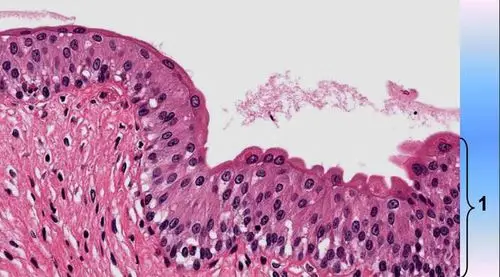

请判断图中1所示的是何种上皮组织?()

p>上皮组织(epithelial tissue),简称上皮(epithelium),由密集排列的